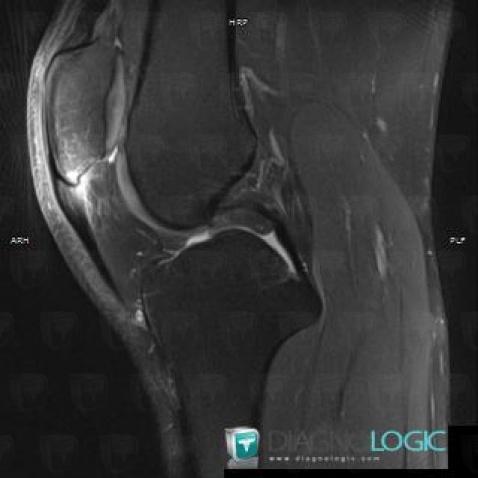

Jumper's knee, Patellar tendon, MRI

Here is the specific information in the key image above:

- Diagnosis Jumper's knee, Location(s) Patellar tendon, with gamuts